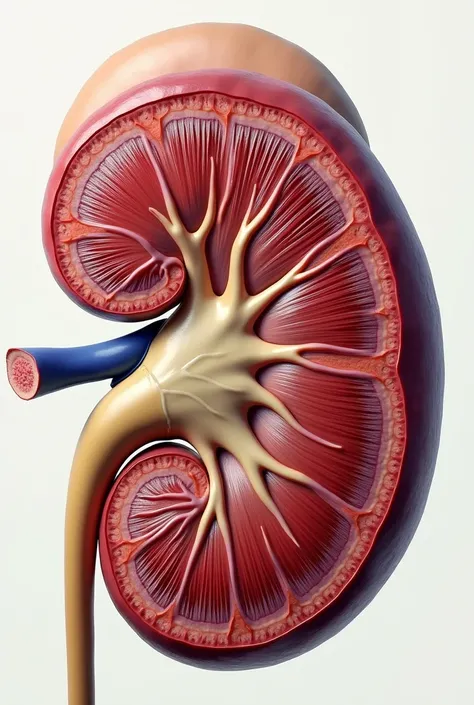

A diagram of the anatomy of the human body